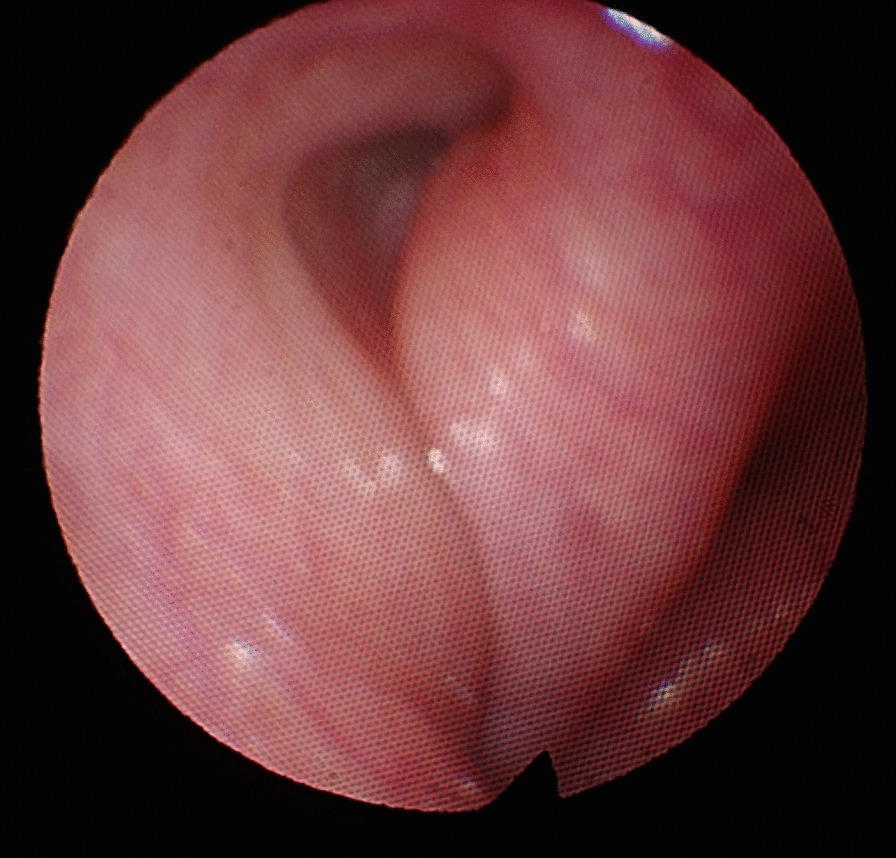

Fig. 4.

Comparison of pre- and postoperative CT (axial view). A preoperative CT, solid arrow points to the eustachian tube. B postoperative CT, solid arrow points to the dilated eustachian tube. C preoperative CT, dash arrow points to carotid canal before dilation. D postoperative CT, dash arrow points to intact carotid canal after dilation of the eustachian tube—no dehiscence can be noted

In all twelve included patients, BDET with the EVB was carried out successfully. The endoscope was placed on the same side as the dilation device in all twelve cases. The malleable suction was used in 6 cases, the 45° device in 4 cases and the 70° in 1 case. In one single case the 45° device was used first, but since placement was not successful, the malleable device was subsequently used. Although the angle of the malleable device could theoretically be bent, it was left in its original position during the entire study period. Intraoperatively minor bleeding from the turbinate was noted in some cases, which was easily controlled with a transient packing of the nose with adrenalin- or xylometazoline-soaked patties. The nasal cavity was not packed postoperatively. No instances of major adverse events occurred. The mucosa was inspected in all twelve patients after dilation and no mucosal tears or abrasions were noted. The procedure time ranged between 15 and 20 min. Postoperative CT was carried out in all twelve cases on the day of surgery to assess for any damages. Special focus was given to the tissue of the eustachian tube and any obvious damages as well as the integrity of the carotid canal in comparison to the preoperative CT. Examples are shown in Fig. 4. None of the CT images showed carotid canal fracture or dehiscence, as well as gross tissue damage. All surgeries were performed in an ambulatory day surgery setting. None of the included individuals reported any adverse events during their time at home following surgery. After two weeks of follow-up, patients were asked about the occurrence of any adverse events. One patient suffered from temporary nasal obstruction for one to two days after the procedure, which was treated with nasal saline sprays. Transnasal endoscopy did not show any swelling at follow-up. No patient reported epistaxis, swelling of the face or emphysema. Pain was not mentioned as an issue by any of the included patients. The orifice of the eustachian tube was inspected at the two-week follow-up in all cases and showed unremarkable results (Fig. 3). There was no sign of infection, bleeding, blood clot, hematoma, infection, edema at the orifice folds, torus tobarius, and nasopharynx. The mean ETDQ-7 score before the surgery was 29.5 (range 7 – 41 points), as opposed to 16 (range 7–39 points) 2 months after dilation. Results of the individual ETDQ-7 questionnaires, tympanograms, average conductive hearing loss (average across 0.5, 1, 2 and 4 kHz) and pure tone audiogram (4-PTA—average across 0.5, 1, 2 and 4 kHz) can be found in Table 1.